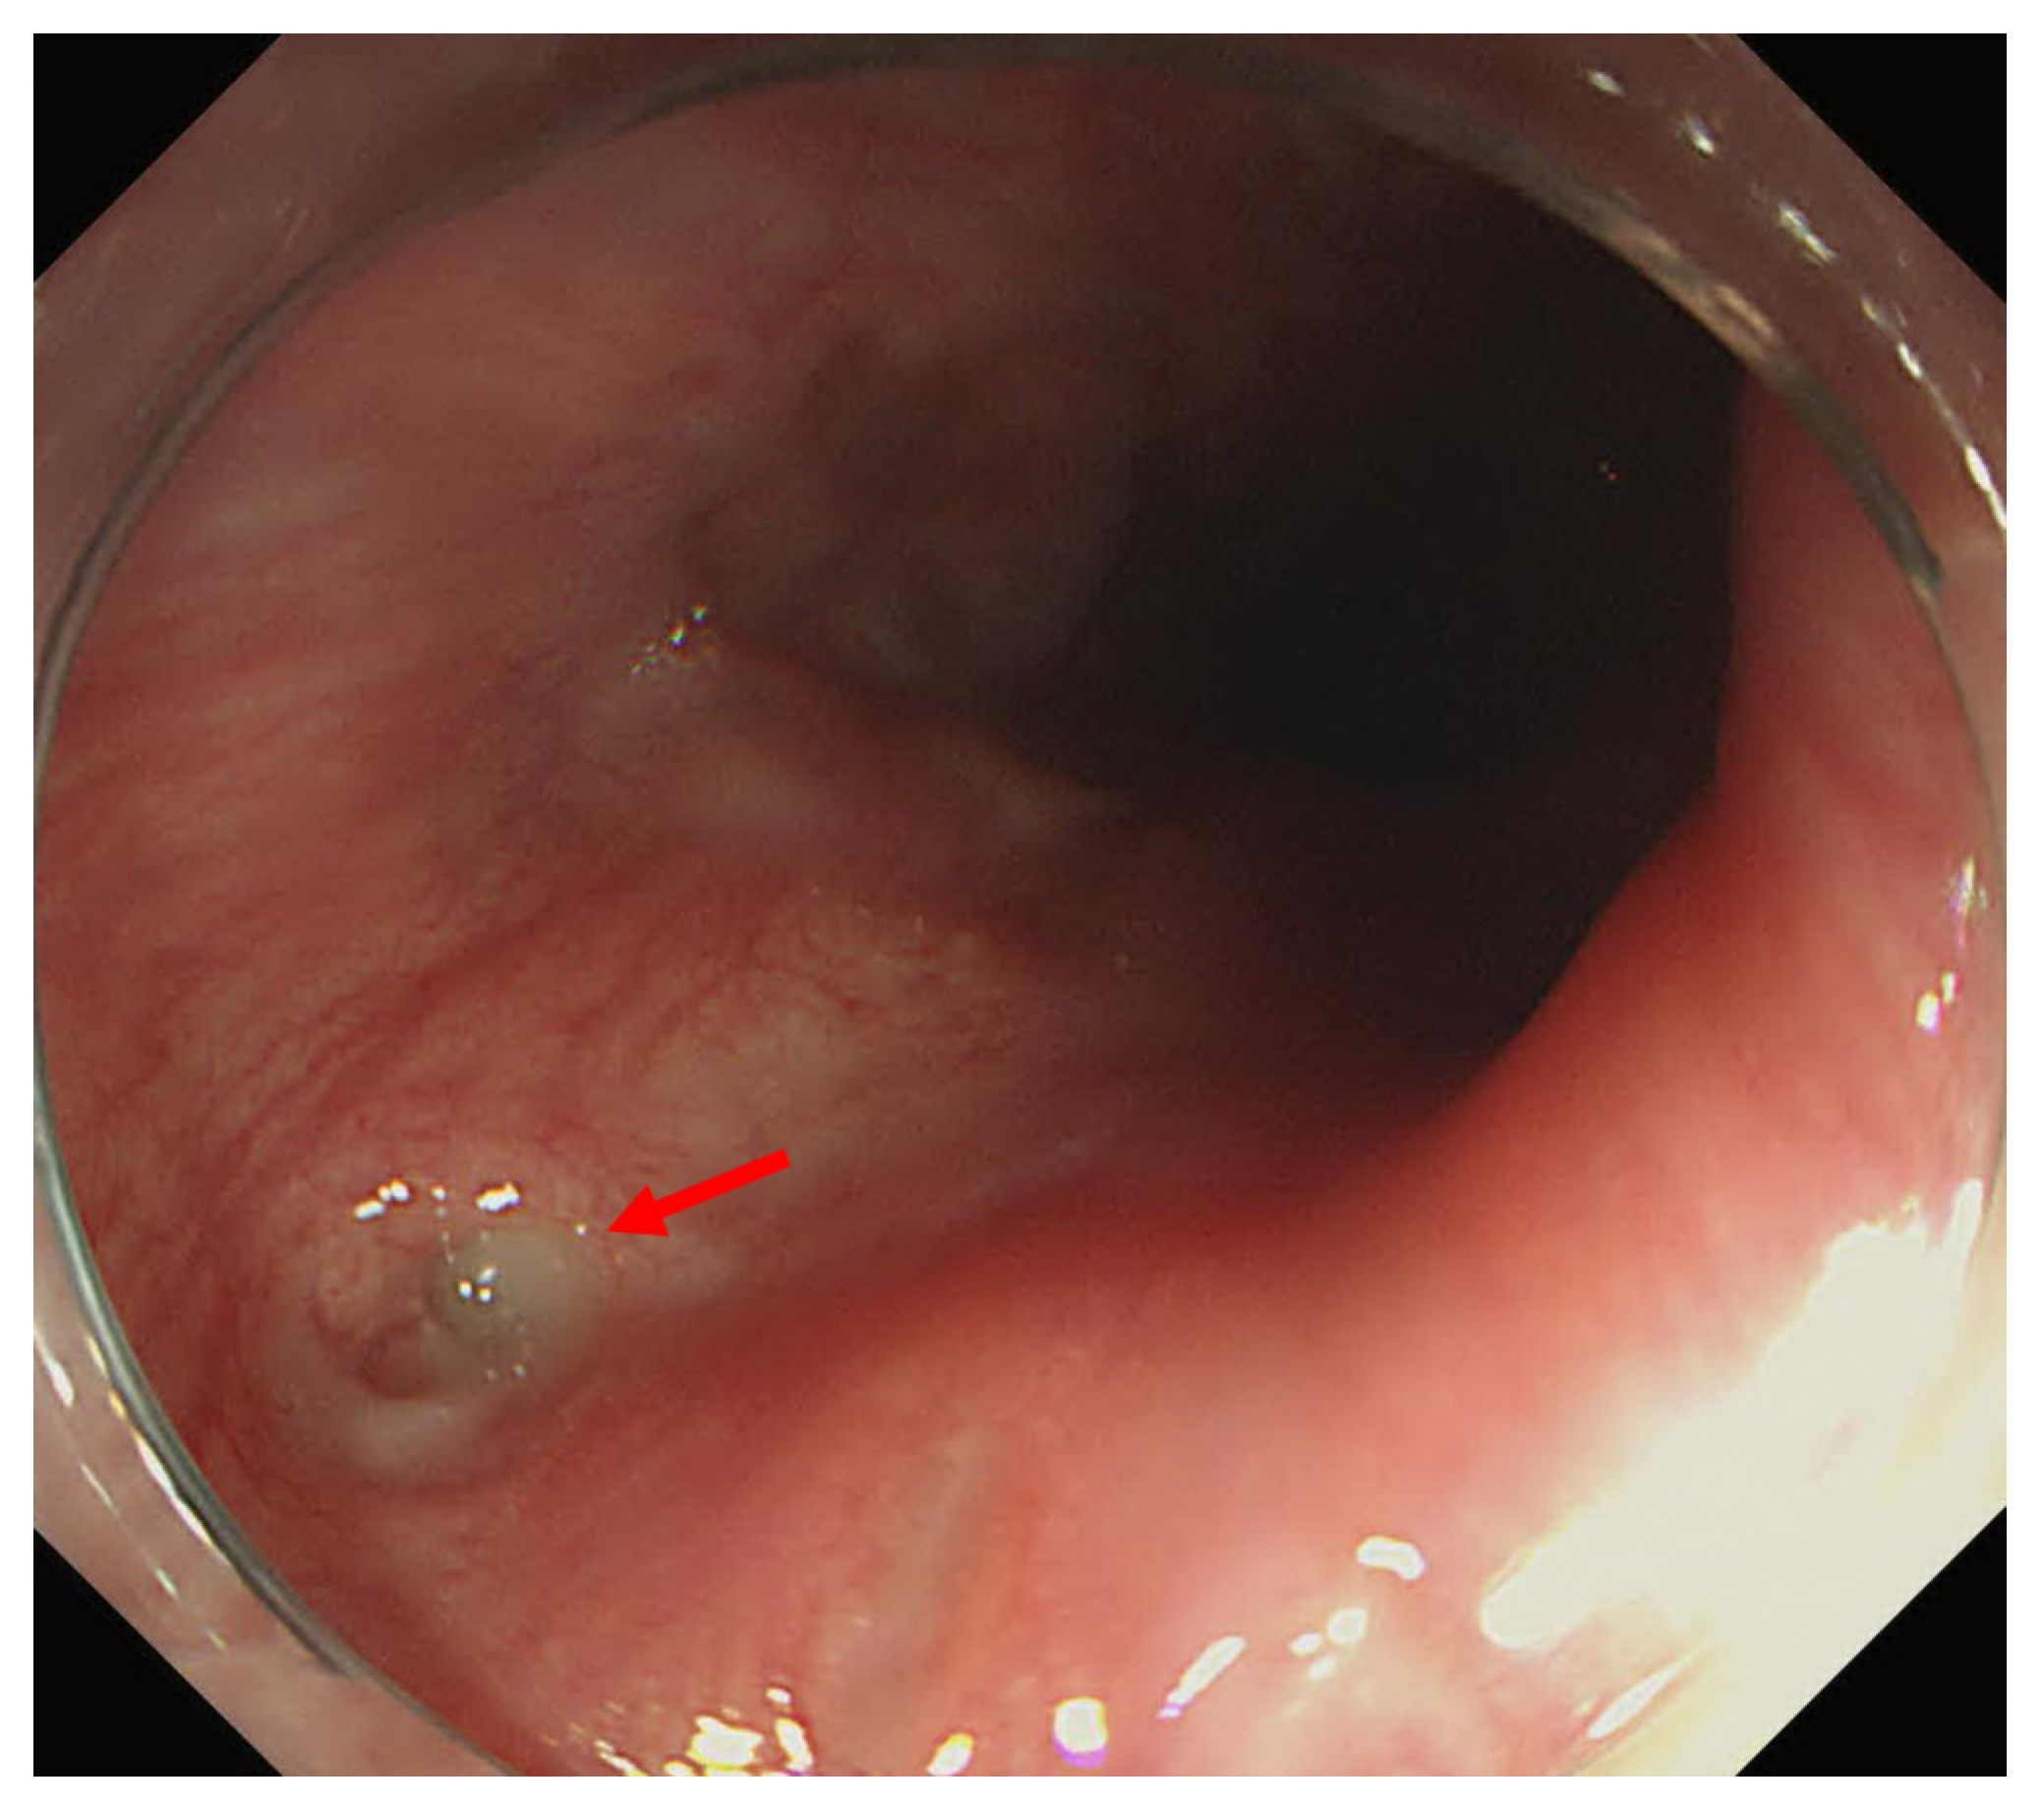

2. Detailed Case Description